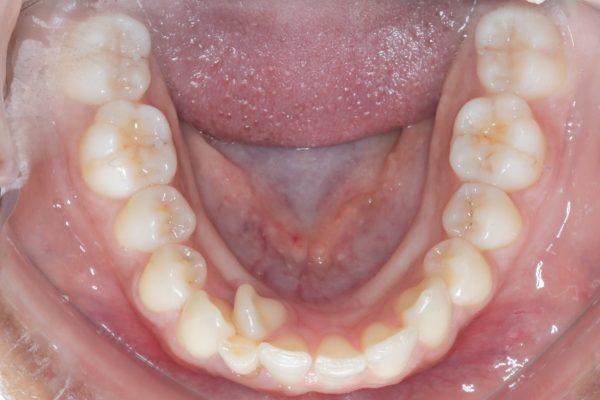

- Crowded or Misplaced Teeth — If the teeth are blocked out, overlapped, or misplaced, it could indicate a lack of space for permanent teeth.